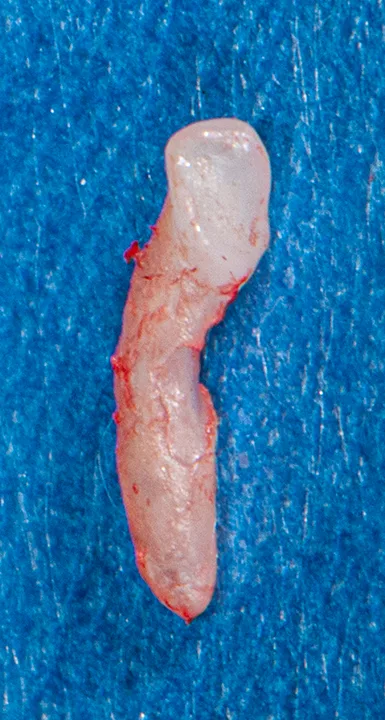

Extracted third incisor from a cat with surface external root resorption extending to the oral cavity

When resorption stops, cells from the periodontal ligament proliferate and populate the resorbed area, depositing reparative tissue. Surface resorption is generally self-limiting unless it is exposed to the oral cavity; this is often quite painful because dentin tubules are exposed to heat, cold, and pressure.